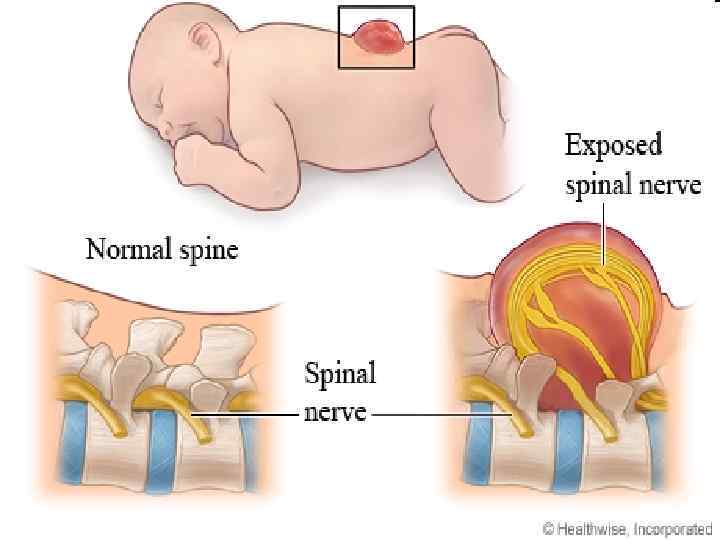

SPINA BIFIDA 111

Менингорадикулоцеле 112

Менингомиелоцеле 113

114

115

Ребенок со spina bifida 116